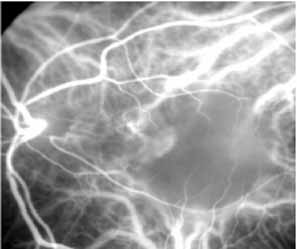

Most promising in this category of inflammatory choroidopathies is a better detection and understanding of the lesions of multifocal choroiditis. Multiple large, scattered, hypofluorescent spots are seen on ICG angiography, particularly in the later phases of the angiogram69 (Fig. 18). These lesions are not evident either on clinical examination or on fluorescein angiography. In addition to having these larger hypofluorescent lesions, patients with multifocal choroiditis have smaller dot-like lesions and hyperfluorescent foci that do not correlate with lesions seen clinically or by FA. They involve the posterior pole and in some patients extend into the mid-periphery. There is also a “papillotropic” involvement, with confluent hypofluorescent lesions surrounding the optic nerve,69 which may be useful in understanding the associated blind-spot enlargement evident in this condition.70 Other zonal visual field defects have been associated with this condition,70 and corresponding ICG abnormalities have been documented in some patients.69

Fig. 18 A. Clinical photograph of a patient with active inflammation associated with multifocal choroiditis. An atrophic scar from previous laser photocoagulation treatment is noted in the temporal macula. The patient reported visual disturbance, and an enlarged blind spot was noted on visual field testing. B. Late-phase indocyanine green study demonstrating a multitude of hypofluorescent spots that were larger than those seen with multiple evanescent white dot syndrome and more numerous and more extensively distributed than appreciated on clinical examination. Note that there is marked confluence of these lesions around the optic nerve, which may help to explain the enlarged blind spot noted on visual field testing.

Natural history data indicate that with progressive increase in vitritis and associated choroidal inflammation, an increase in the number and extent of these hypofluorescent lesions can be documented.40 Furthermore, use of oral steroid therapy as a means of controlling this inflammatory process has been documented to produce not only clinical resolution of the inflammatory process but also corresponding resolution of the hypofluorescent lesions seen on ICG angiography.69 These clearly demonstrated lesions not only may lead to a better understanding of the process of inflammation involved in multifocal choroiditis and potential management strategies but also may serve to differentiate this condition from the ocular histoplasmosis syndrome.